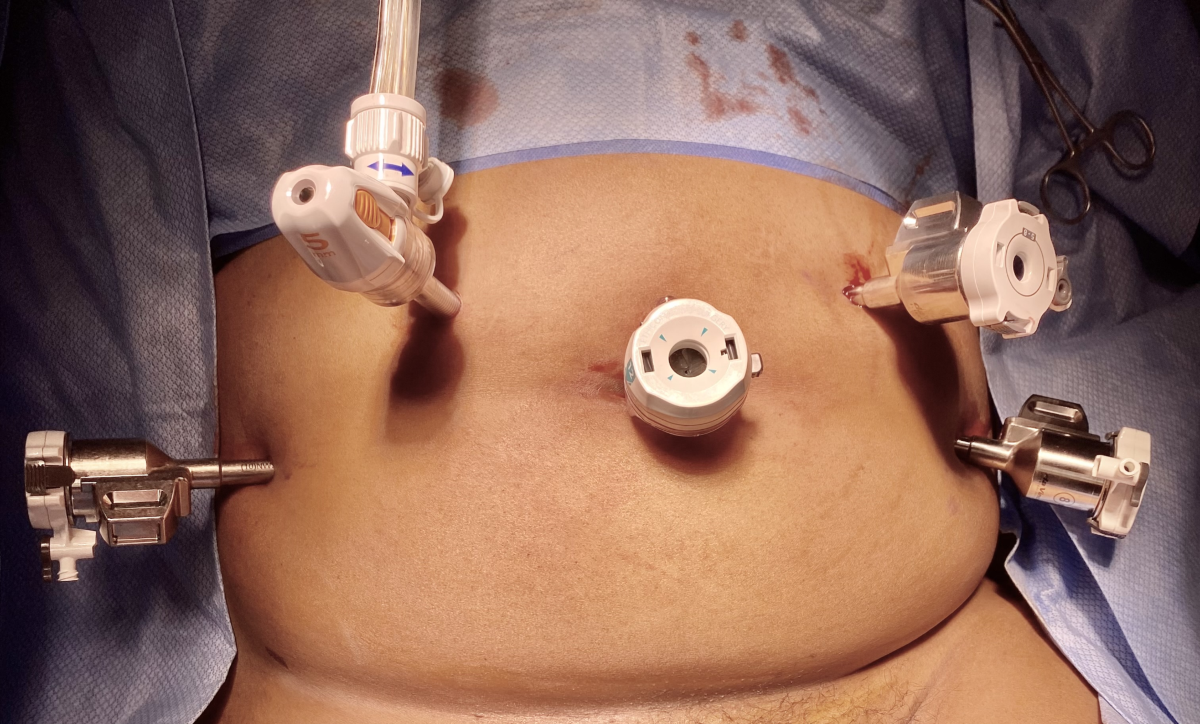

Unlike traditional open surgery, this procedure uses small incisions and a specialized camera to guide the removal of fibroids. The uterus is repaired carefully after the fibroids are removed.

The surgery is performed under general anesthesia. Small incisions are made in the abdomen to insert a laparoscope and surgical instruments. The fibroids are carefully separated from the uterine wall and removed. The uterine muscle is then sutured securely to maintain strength for future pregnancies.